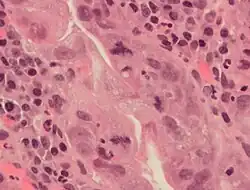

Diagnostic marker

In histopathology, the mitosis rate (mitotic count or mitotic index) is an important parameter in various types of tissue samples, for diagnosis as well as to further specify the aggressiveness of tumors. For example, there is routinely a quantification of mitotic count in breast cancer classification.[74] The mitoses must be counted in an area of the highest mitotic activity. Visually identifying these areas, is difficult in tumors with very high mitotic activity.[75] Also, the detection of atypical forms of mitosis can be used both as a diagnostic and prognostic marker. For example, lag-type mitosis (non-attached condensed chromatin in the area of the mitotic figure) indicates high risk human papillomavirus infection-related cervical cancer. In order to improve the reproducibility and accuracy of the mitotic count, automated image analysis using deep learning-based algorithms have been proposed.[76] However, further research is needed before those algorithms can be used to routine diagnostics.